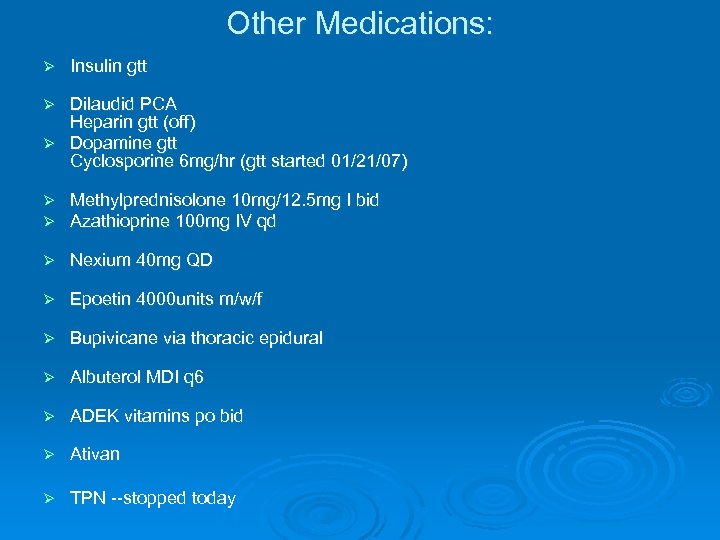

Other Medications: Ø Insulin gtt Dilaudid PCA Heparin gtt (off) Ø Dopamine gtt Cyclosporine 6 mg/hr (gtt started 01/21/07) Ø Ø Ø Methylprednisolone 10 mg/12. 5 mg I bid Azathioprine 100 mg IV qd Ø Nexium 40 mg QD Ø Epoetin 4000 units m/w/f Ø Bupivicane via thoracic epidural Ø Albuterol MDI q 6 Ø ADEK vitamins po bid Ø Ativan Ø TPN --stopped today